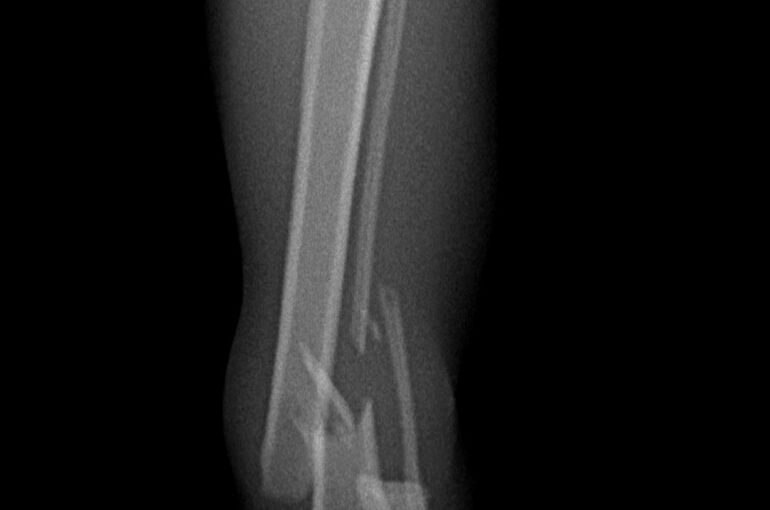

今日はネコちゃんの脛骨(膝下の骨)の骨折治療について報告します。10歳のネコちゃんですが、高いところから飛び降りたときにバランスを崩して着地に失敗して骨折したようです。

痛々しい画像ですが、実際もかなり痛がっていて興奮していたので軽く鎮静をかけてレントゲン撮影しました。